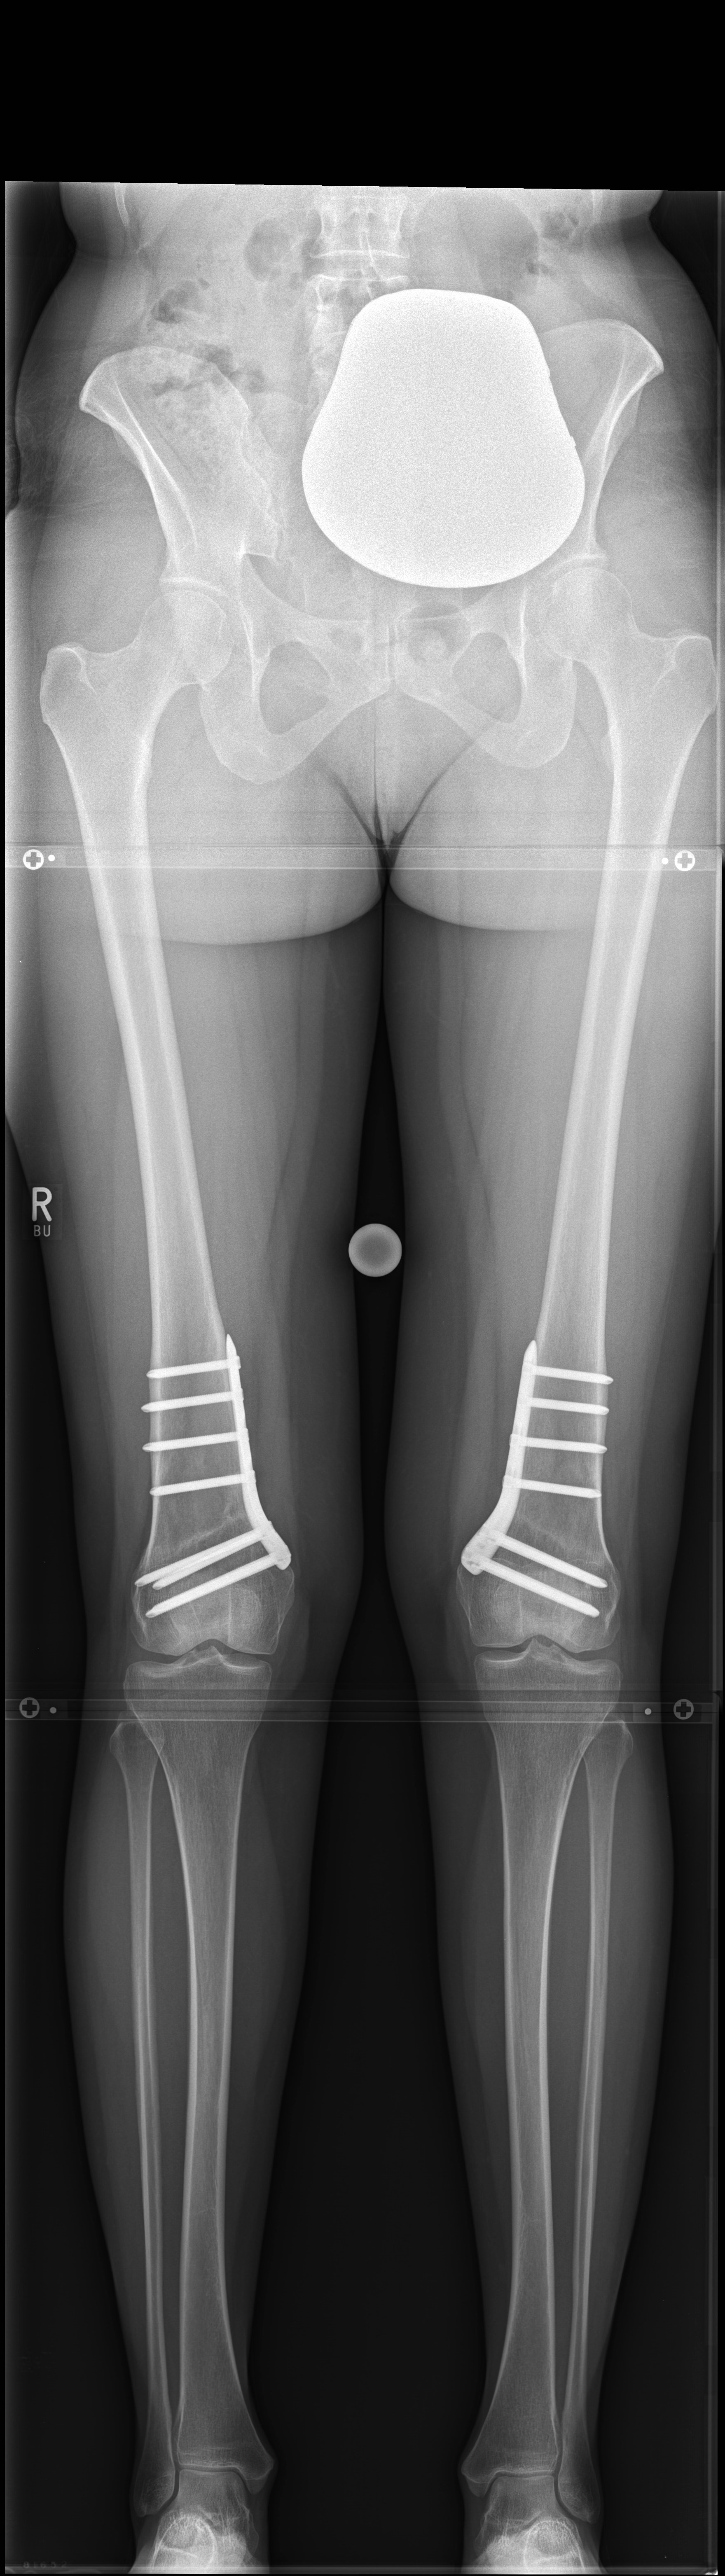

Case 3

(Case provided by Steffen Schröter)

A 52-year-old man, a heavy worker was still able to work, however he was administered pain killers. During weekends only brief bike rides were tolerable. He reported an effusion and on that evening further daily activities were not possible. He complained of pain in the medial compartment. Excessive bowing legs were noticeable. Ligaments were stable in the sagittal plane but there was a medial instability in the coronal plane because of damage to the cartilage. He underwent double-level osteotomy for correction of the leg alignment.

Showcasing a double-level osteotomy case